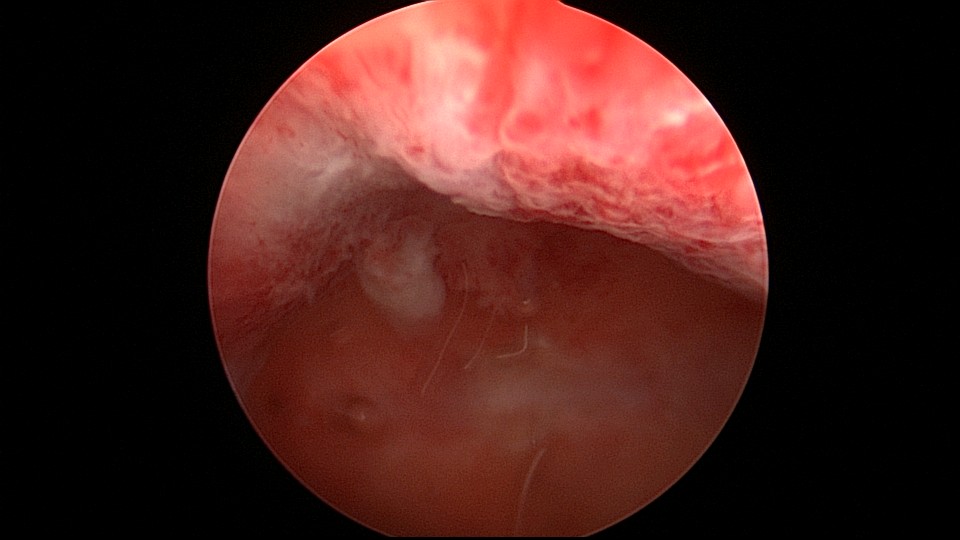

患者21岁,G2P0,两次胎停清宫,月经量减少,眉山某医院B超示宫腔容积小,2021年7月宫腔镜探查,见宫腔两侧、宫底部及左侧宫角粘连,单极电针分粘,恢复宫腔形态,显露双侧输卵管开口。2021年9月宫腔镜二探取球囊,宫腔形态正常,双侧输卵管开口可见。2022年9月自然妊娠12+周,我院建卡,2023年5月孕38+周剖宫产分娩。2025年3月宫腔镜取胚1次,现25岁,G4P1,剖宫产1次。